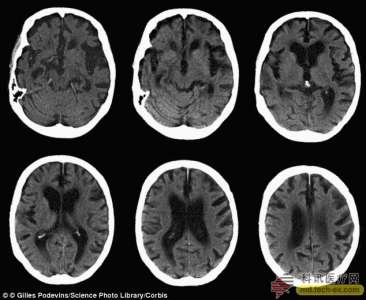

新的线粒体DNA检测技术可以早期诊断老年痴呆

据报道科学家希望通过新的检测技术在阿尔茨海默综合症(老年痴呆)出现症状十年前检出该病症,为早期治疗奠定基础。

某个特定类型的遗传物质水平的下降可能是增加阿尔茨海默发病风险的信号。这种在脑脊液中的生物标记物能在老年痴呆出现十年前被检测到。

在西班牙的巴塞罗那生物医学研究所的研究人员认为他们已经找到一个生物标记物,它能在症状出现之前揭示疾病的进展过程。他们发现在脑脊液中线粒体DNA(MtdDNA)含量的下降可能是该病发生的信号。

他们介绍说mtDNA含量的下降反应了线粒体为脑细胞供能的能力减弱,从而触发脑细胞死亡。

mtDNA浓度的下降要先于阿尔茨海默病其它生化标志物出现,这表明该病的发生要比我们以前认为的更早,mtDNA是该病最早的标志物之一。